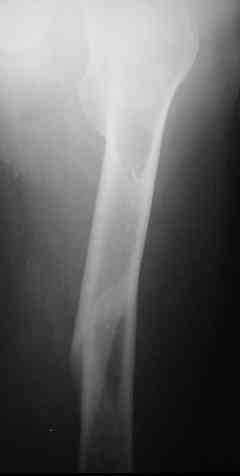

Уважаемые коллеги,пару дней назад к нам поступил пациент 54 лет с таким вот переломом правого бедра. Сейчас на скелетном вытяжении. Хотелось бы услышать мнения по поводу природы округлого просветления в подвербельной области (аневризмальная киста?)и тактики лечения.

Dear all, a few days ago a 54 y.o. patient was admitted to our hospital with this fracture of the right femur. Now he is on a skeletal traction. I'd appreciate your opinion as to: 1.the nature of a lucent lesion (?) in subtrochanteric area - is it ABC? 2.treatment options.Thanks, Peter Romchuk, Central City Hospital, Rivne, Ukraine.С уважением, Петр Ромчук, ЦГБ г.Ривне, Украина

По предъявленным снимкам более вероятны следующие дифференциальные диагнозы:

1. энхондрома

2. фиброма

для аневризмальной кисты нет истончения и вздутия кортикального слоя, также не подходит возраст пациента (АКК выявляется в период от 5 до 30 лет)

конечно, необходимо прицельно снять проксимальный отдел бедра, так как по показанным снимкам не понятно, переходит очаг перестройки на б.вертел и шейку, или нет.